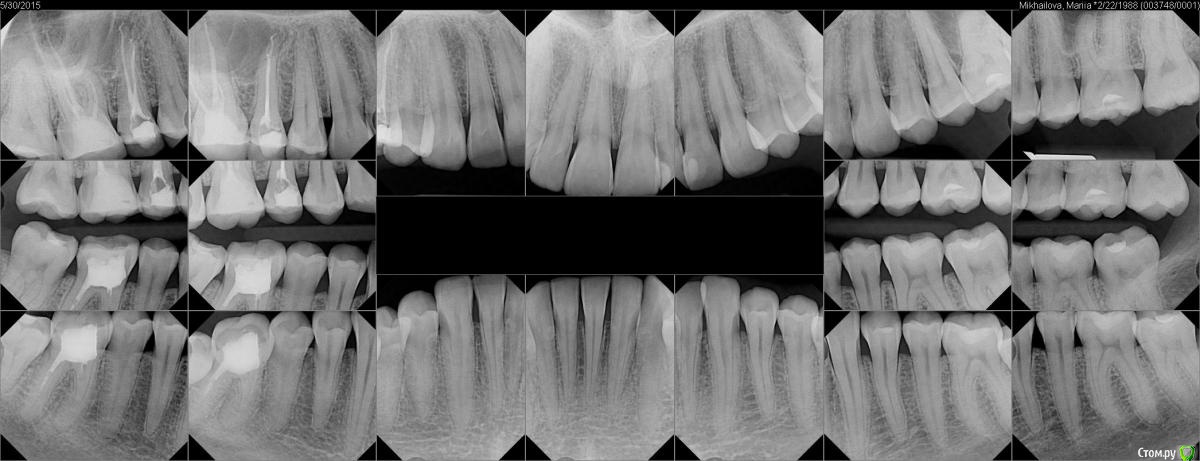

finitezza Опубликовано 3 июня, 2015 Поделиться Опубликовано 3 июня, 2015 Всем привет, подскажите пжта!Что это за потемнение около 26 зуба, в левом верхнем углу на снимке?Его лечила лет 5 назад, а 25, на днях лечила ( на снимке временная пл.). Ссылка на комментарий

red_butler Опубликовано 3 июня, 2015 Поделиться Опубликовано 3 июня, 2015 Это верхнечелюстной синус (гайморова пазуха) Ссылка на комментарий

finitezza Опубликовано 3 июня, 2015 Автор Поделиться Опубликовано 3 июня, 2015 Это верхнечелюстной синус (гайморова пазуха)А на другой стороне вроде нет этого, это нормально? Ссылка на комментарий

red_butler Опубликовано 3 июня, 2015 Поделиться Опубликовано 3 июня, 2015 А на другой стороне вроде нет этого, это нормально?на другой тоже есть, это нормально Ссылка на комментарий

finitezza Опубликовано 3 июня, 2015 Автор Поделиться Опубликовано 3 июня, 2015 на другой тоже есть, это нормальноСпасибо огромное, за ответ!Еще вопрос, что можно сказать по снимку? Мне говорит доктор каналы лечить на других 2х зубах, и ставить коронки, коронки конечно нужны, но нижний зуб 36 вроде, давно лечили, и все нормально, правда по снимку видно, что один канал не совсем заполнен. Может все таки так можно походить пока?Как вы считаете? Ссылка на комментарий

red_butler Опубликовано 3 июня, 2015 Поделиться Опубликовано 3 июня, 2015 Как вы считаете? Ваш врач прав, 3.6 перелечить и три зуба протезировать Ссылка на комментарий